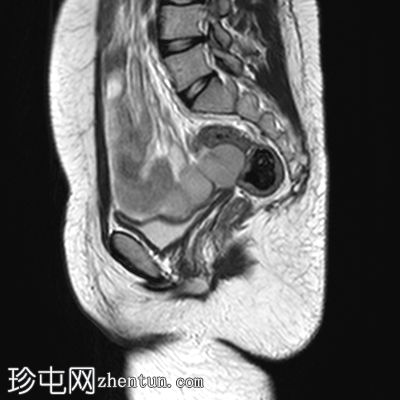

轴位

T2加权像

子宫缺失

卵巢缺失

阴道下三分之一发育不全,上三分之二缺失

可见双侧腹股沟卵圆形结构,提示隐睾(右侧约2.4×2厘米,左侧约2.3×2厘米)

上述特征符合雄激素不敏感综合征(睾丸女性化综合征)的典型表现。

核型分析显示46XY染色体。